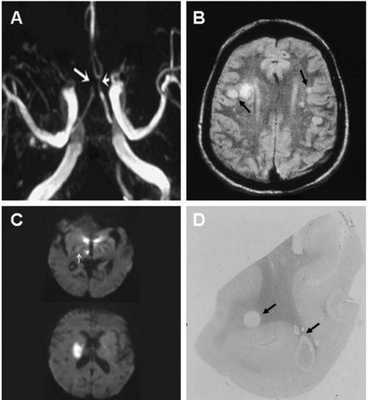

(А) времяпролетная МР-ангиограмма демонстрирует расширение левой (короткая стрелка) и окклюзию просвета правой (длинная стрелка) передних мозговых артерий

(В) МР-скан головного мозга определяет множественные гиперинтенсивные области в обеих гемисферах, в основном локализованные в белом и на границе серого и белого вещества (стрелки).

(С) При использовании последовательности DWI определяются участи ограничения диффузии (что отвечает ишемии) в таламусе, гипотоламусах и задней части внутренней капсулы справа (стрелка). Неделю спустя у пациента развилась картина гемиплегии.

(D) Макроскопические изменения у пациента, умершего в результате хронической васкулопатии. Овоидной формы множественные участки ишемии и демиелинизации.

- умеренное ограничение диффузии в областях цитотоксического отека и

- зоны ишемии проявляются выраженным ограничением диффузии.